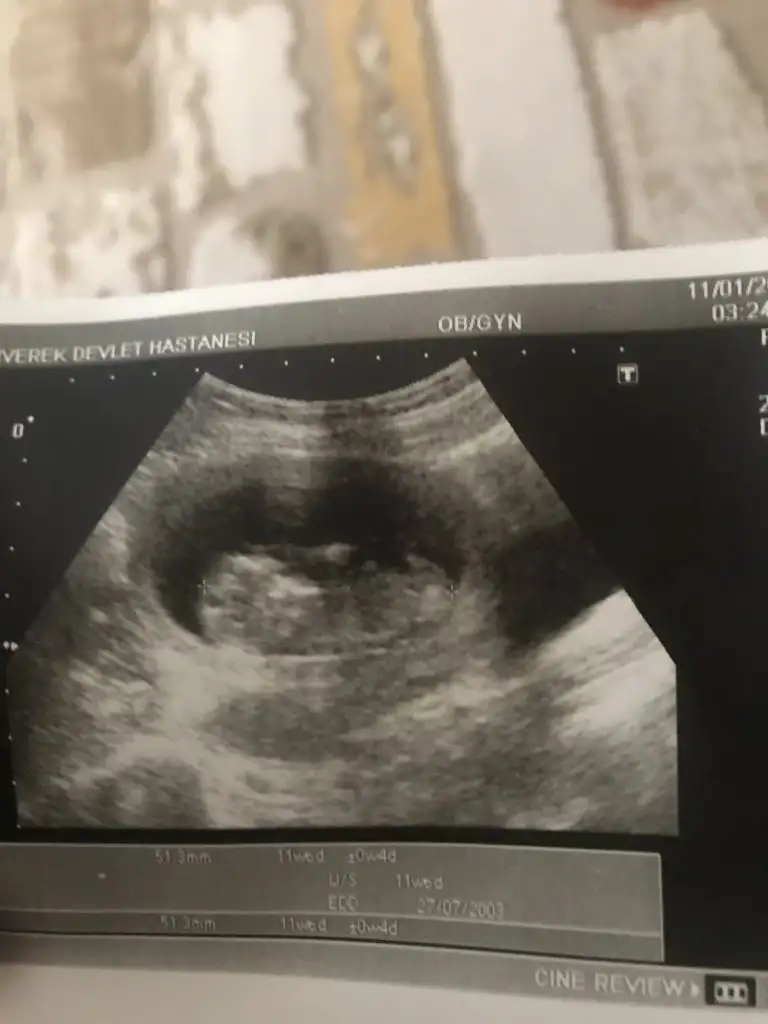

Net degil usg gördügüm nub ise erkek gibi başka varsa usg 11 yada 12 hafta paylaşın bu usg kaç haftalıkbanada tahminde bulunurmusunuz rica etsem

Erkektir o zamanbu usg 12 +3 haftalık doktor %90 erkek dedi bu perşembe netleşecek